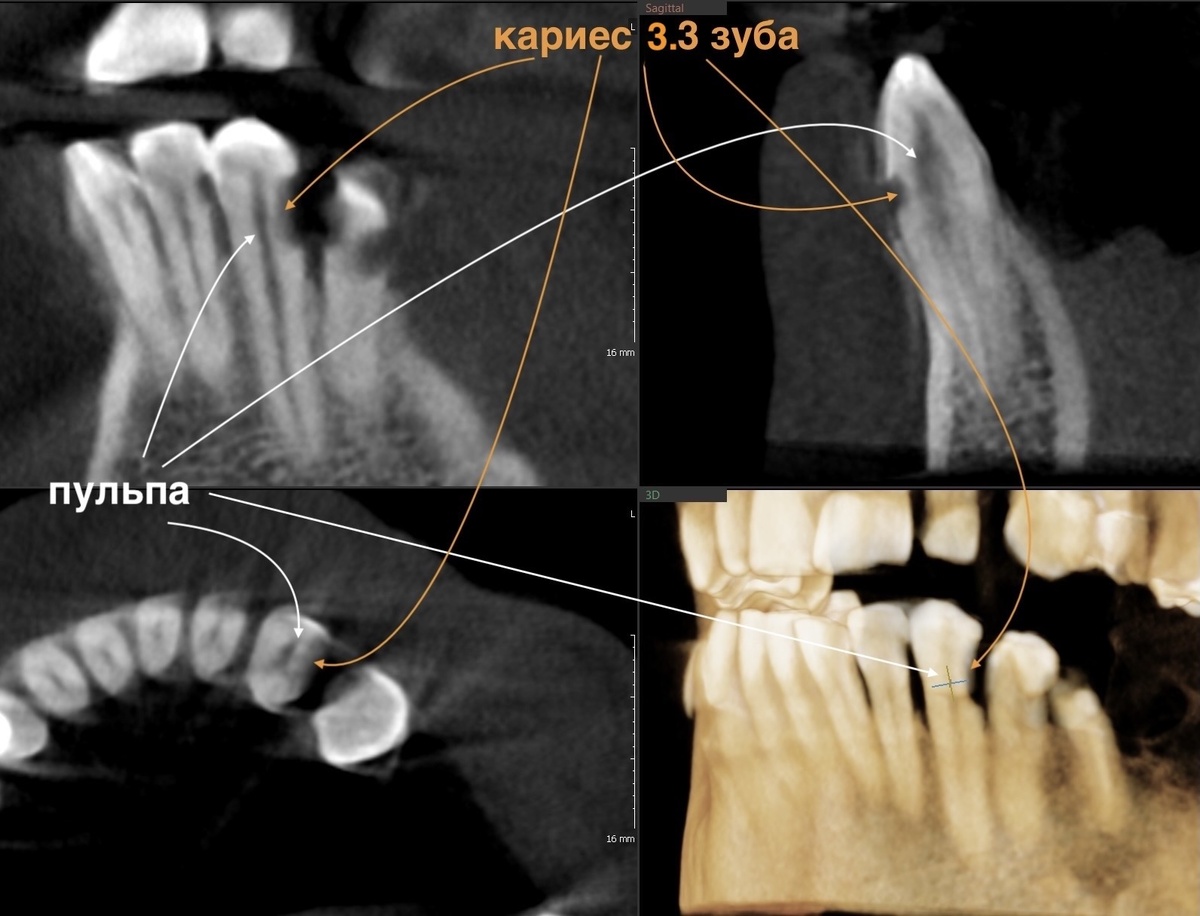

Вспомним старую компьютерную томограмму, ещё до лечения сделанную, самые экстремальные полости оценим:

Меньше миллиметра тканей отделяет кариозные полости от нерва. При таких глубоких поражениях многие депульпировали бы зубы "для надёжности".

И пациенты, часто, того же мнения придерживаются - надёжнее удалить нерв. Собственно, так и есть. Но есть врачи, которым под силу оставить зуб живым даже в такой сложной ситуации и делают они это на потоке. Для них это не чудо, а работа.